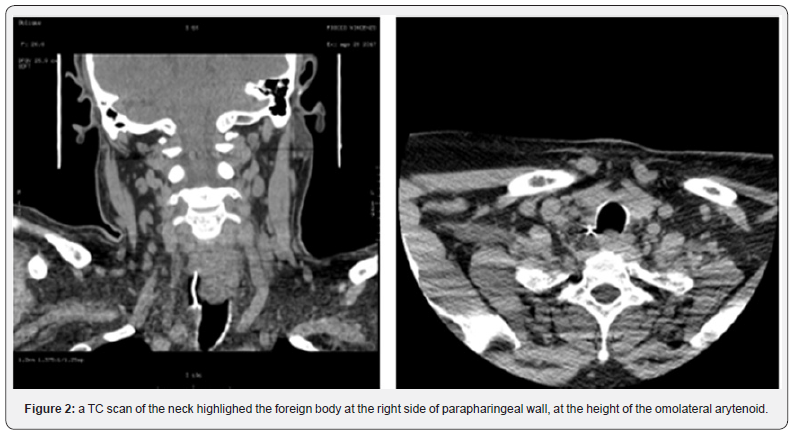

50-year-old men, V.F., presented to our ENT department due to a severe dysphagia that appeared about 5 days earlier after a fish-based lunch. The patient was convinced he had ingested a fish hook. The endoscopic evaluation of the high airways showed an important edema of the right arytenoid; the vocal cords were normal in form and motility, and no foreign body was visible. However, the X-ray of the esophageal-pharyngeal tract Figure 1 showed a suspected extraneous oesophageal body by ingestion of food and signaled, at C5-C6 level on right side of parapharyngeal wall, a 45 mm linear radiopac image. An integration with endoscopic examination was required. However, esophagogastroduodenoscopy was negative for the presence of foreign bodies,but it showed the presence of an extraneous granuloma at the level of the right arytenoid.In the same day, in general anesthesia, apanendoscopy of the superior aero-digestive tract was performed, which does not show any extraneous body at this level, except an important congestion of the right piriform sinus. At the end of the procedure, a nasal-gastric tube was due to a suspected perforation of the esophagus. At this point, the hypothesis that the right piriform sinus was been the point of entry of the foreign body became more and more concrete.A TC scan of the neck (Figure 2) was performed and it highlighted the foreign body at the right side of parapharyngeal wall, at the height of the homolateralarytenoid. Therefore, we decided to undergo a cervicotomicsurgery. In general anesthesia, cutaneous incision was performed along the margin of the sternocleidomastoid muscle, about 10 cm. The right thyroid lobe was found and lowered from the lateral wall of the trachea to the side wall of the esophagus, which had a millimetric puncture (foreign body output point). In the tracheo-esophageal sulcus, near the right recurrent nerve, the foreign body (metal wire about 5 cm in length) Figure 3 was found and removed.